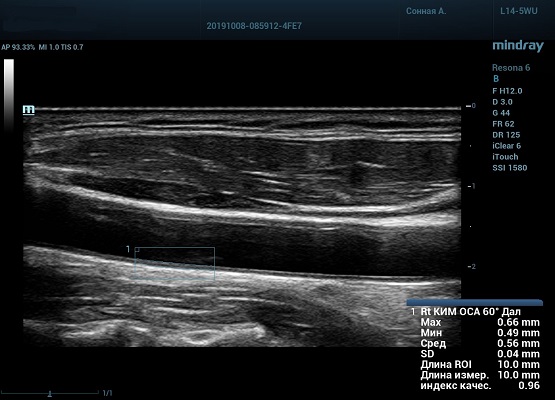

Функция в ультразвуковых аппаратах

На сегодняшний день измерение IMT происходит автоматическим путем при использовании функции AUTO-IMT. Необходимо указать прибору зону интереса, стандартной длиной (1 см), в которой происходит отслеживание кромок и выдача максимального, среднего и минимального значения. УЗИ аппараты компании Mindray среднего, экспертного и премиального класса снабжены данной функцией и позволяют контролировать не только полученные значения, но и оценить точность измерения кромки в конкретной зоне по индексу качества. Используя индекс качества, легко решить, можно ли использовать полученное значение.